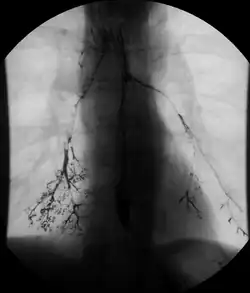

Normal barium swallow fluoroscopic image, showing the ingested barium sulfate being induced down the oesophagus by peristalsis.